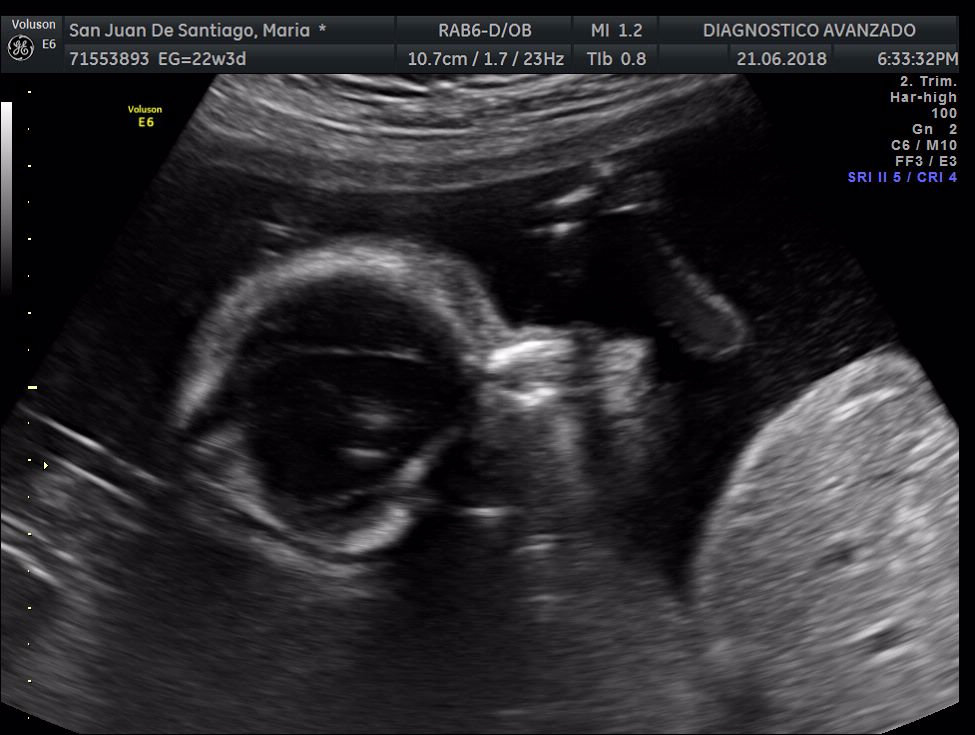

¡Hola a todos! Hoy hemos ido a hacer la tradicional ecografía 3D de la niña, os dejamos todo el material (aunque es un poco demasiado).